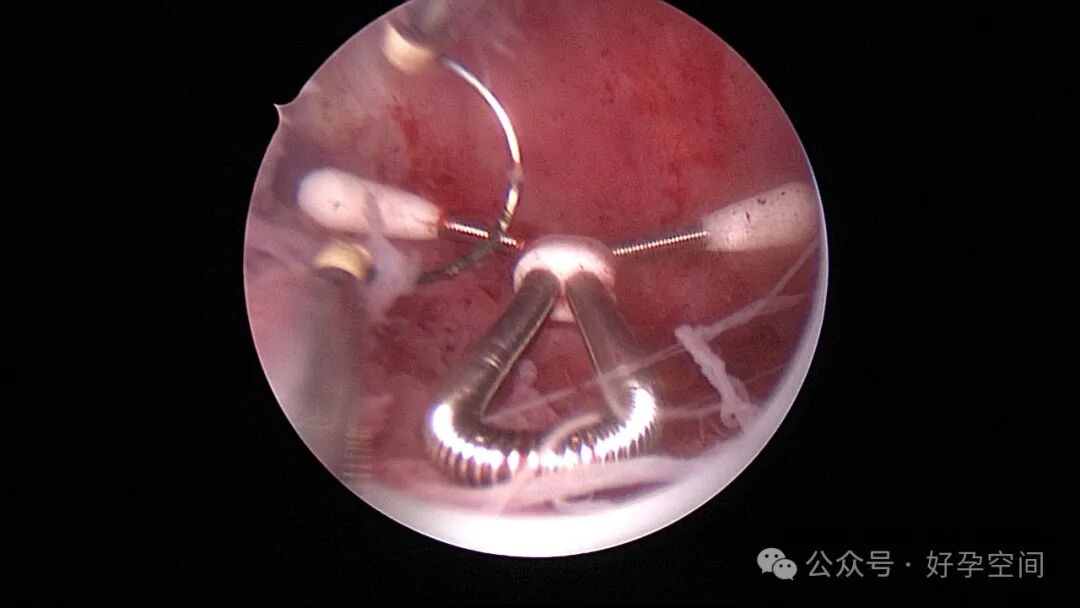

患者24岁,G6P3,顺产1次,双胎剖宫产1次。本次停经53天,计划外妊娠,行宫腔镜取胚及安环术。摘除胚胎后见宫腔右侧壁胚胎附着部位包块,约1.0cm*1.0cm*0.8cm,宫腔镜切除包块送病检,放置γ环一个,环两臂卷曲于右侧宫角,宫腔镜钩住环尾部下拉,上推节育环右臂,将环调整到正常位置。术后病检结果为“宫腔胎盘附着部位超常反应”。